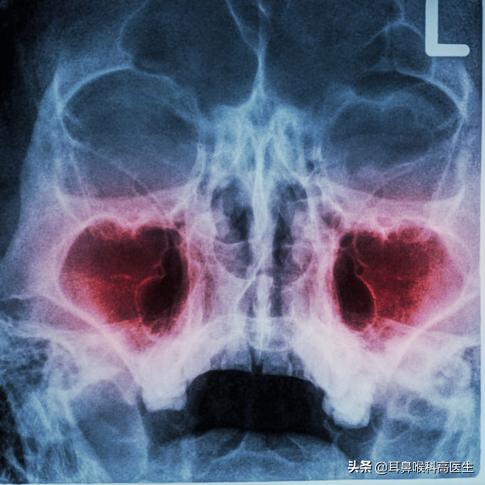

临床工作中,有部分患者反反复复的头痛,头痛甚至影响工作及生活。到处就医,做过很多检查及治疗,有的说神经性头痛,有的说血管性头疼,有的说颈椎引起头痛,做过相应检查及治疗都没有效果,还尝试中医的调理,但收效甚微。有很多患者担心脑子里有问题,做了头部CT,发现鼻窦炎症明显,头痛很有可能就是鼻窦炎引起,但这些患者鼻腔症状没有或者比较轻微,鼻窦炎为什么会表现出头痛?

我们有四对鼻窦,鼻窦所在头部的位置不同,表现也不一样,下面逐一介绍鼻窦引起头痛原因及各鼻窦引起疼痛的表现:

- 鼻窦头痛原因:鼻窦开口于鼻腔外侧壁的空腔,当鼻窦炎症,鼻腔黏膜肿胀厉害,加上鼻腔脓性分泌物增多潴留,鼻窦压力增高,就出现头痛,脓液刺激还会出现头昏症状;当鼻腔脓性分泌物排除后,鼻窦口肿胀厉害,空气很难进入鼻窦,鼻窦就会出现负压,也就是真空性头痛。